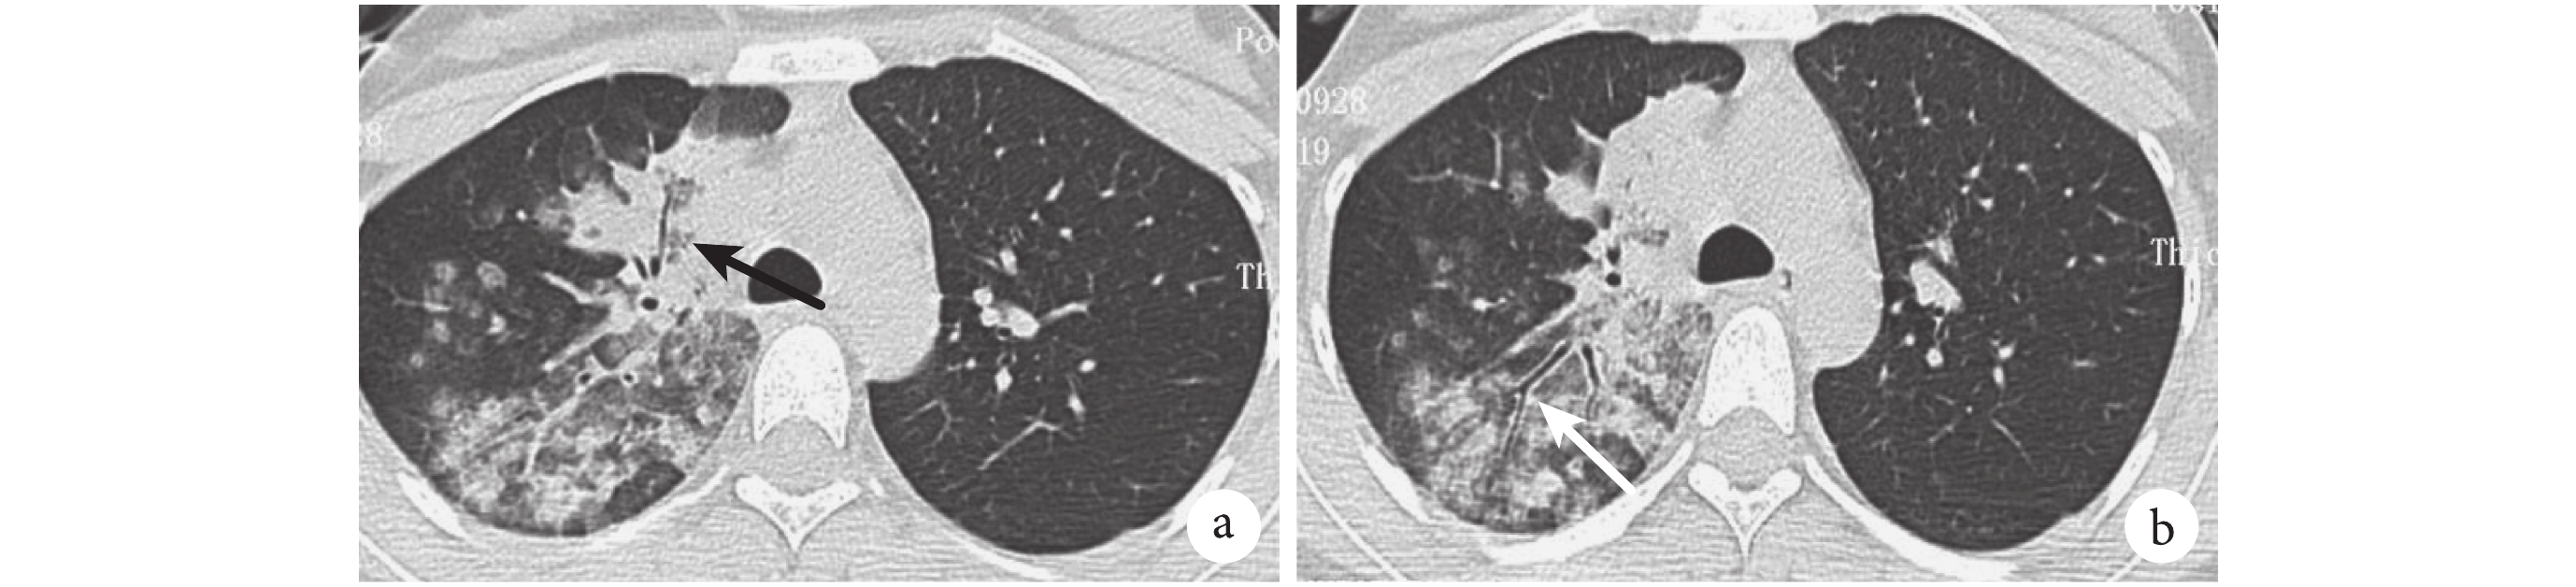

患者,女,66 歲,根據臨床癥狀、實驗室檢查及影像學診斷右側肺炎。右肺上葉片狀分布實變影,多個層面可見斷續 ABG(黑箭),伴有右側少量胸腔積液

患者,女,21 歲,結合癥狀及影像學表現,診斷右側肺炎。a. 右肺多發斑片狀實變影,其內可見斷續 ABG(黑箭);b. 右肺斑片狀滲出中見支氣管壁增厚(白箭)

圖 1~4 展示了 2 例 CAP 及 2 例 OP 患者的胸部 HRCT 影像學特征。在實變影的分布上,69.6% 的 OP 患者呈雙側分布,顯著高于 CAP 組的 30.3%(χ2=22.412,P=0.000)。分別有 41.4% 和 16.1% 的 OP 患者實變影呈胸膜下(圖 1)、支氣管血管周圍(圖 2)分布,在 CAP 組分別為 19.2% 和 1.0%,差異有統計學意義(χ2=8.886,P=0.003;P=0.000)。87.5% 的 OP 患者胸部 HRCT 上有數量不等、形態各異的 ABG,顯著高于 CAP 組的 72.7%(χ2=4.558,P=0.033)。OP 患者的 ABG 數量的中位數及四分位數間距為 4(2~8),顯著高于 CAP 組的數量 2(0~4)(z=3.640,P=0.000)。在形態上,58.9% 的 OP 患者存在 EABG(圖 1b、圖 2a),顯著高于 CAP 組的 21.2%(χ2=22.413,P=0.000)。26.3% 的 CAP 患者有斷續 ABG(圖 3、圖 4),16.1% 的 OP 患者有斷續 ABG(圖 2b),差異無統計學意義(χ2=2.125,P=0.148)。

間質性肺炎的其他征象如牽拉性支氣管擴張(圖 1b、圖 2a)、磨玻璃影(ground glass opacity,GGO)在 OP 患者中更多見,分別為 26.8% 和 39.3%,而在 CAP 組僅為 1.0% 和 11.1%。1.0% 的 CAP 患者有反暈征,顯著低于 OP 組的 26.8%(圖 1a、圖 2a)(χ2=25.671,P=0.000)。胸腔積液(圖 3)和支氣管壁增厚(圖 4b)在 CAP 患者中更常見,為 56.6% 和 35.4%。其他影像學特征詳見表 3。